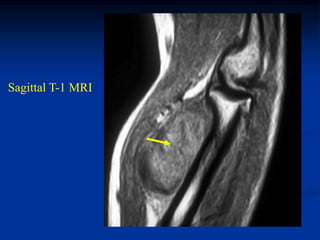

Case #1194

41 year male with

angiolipoma thigh

Coronal T-1 MRI

Axial T-1 MRI

Case #1194 41 yearmale with angiolipoma thigh Coronal T-1 MRI